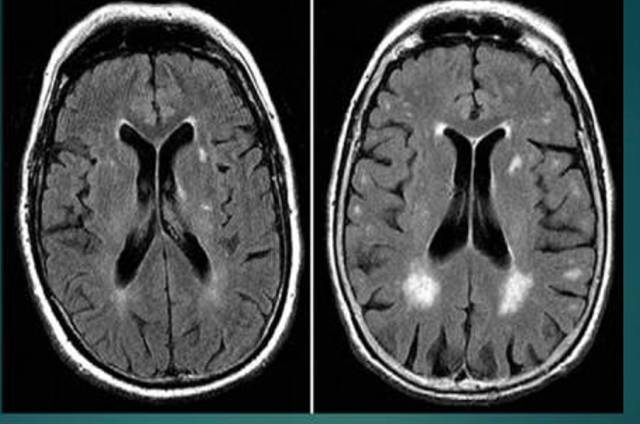

2. 把脑白质点状的脱髓鞘病灶误认为腔梗

文章插图

脑白质病变与腔梗都属于小血管病变 , 最主要的病因都是高血管病 。 脑白质病变一般呈片状 , 主要的好发部位是侧脑室体的旁边 , 内囊区域也会出现 , 大部分在皮层下白质 。 点状脱髓鞘病变与腔梗进行鉴别:脱髓鞘的病变一般两边对称 , 腔梗不对称;脱髓鞘边界不如脑梗死的清楚 。